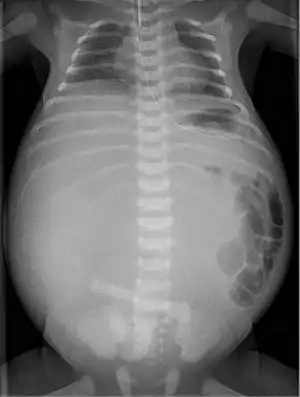

Radiograph with double bubble sign indicating duodenal atresia

If not diagnosed in utero, infants with intestinal atresia are typically diagnosed at day 1 or day 2 after presenting with eating problems, vomiting, and/or failure to have a bowel movement.[3] Diagnosis can be confirmed with an X-ray, and typically followed with an upper gastrointestinal series, lower gastrointestinal series, and ultrasound.[5][3]